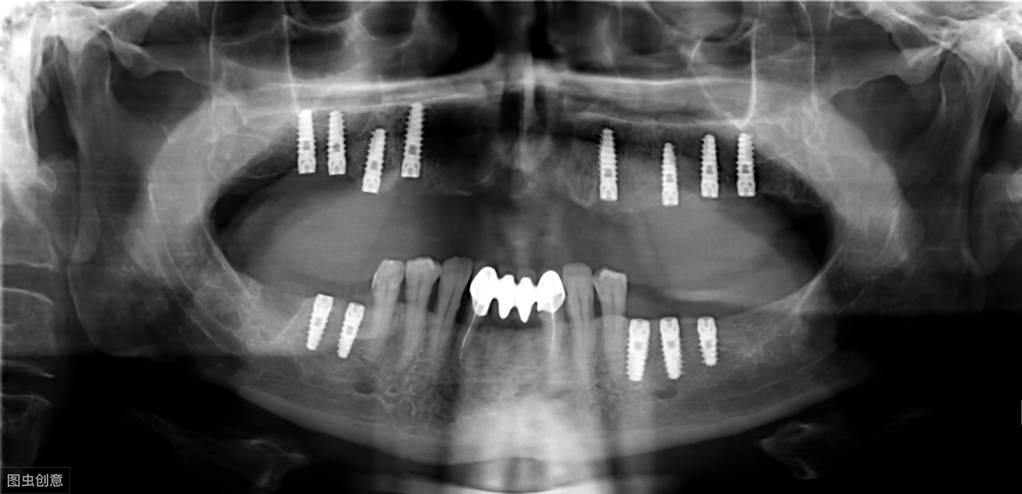

種植牙手術(shù)示意圖

種植牙技術(shù)是近幾十年出現(xiàn)在大眾視野中的一種修復(fù)缺失牙體的方法。一顆完整的種植牙體由三部分組成:種植體、基臺、人工牙冠。

手術(shù)過程就是將種植體植入患者的牙體缺失處,待其傷口愈合,種植體與牙槽骨結(jié)合牢固后,將基臺安裝在種植體上,再將人工牙冠安裝在基臺上,形成完整而堅固的人工牙體。